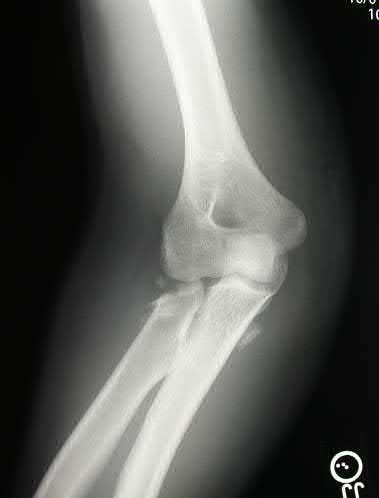

A 72-year-old woman falls down stairs and sustains the injury shown in Figure A. Additional radiographs are performed in Figure B to help assess the fracture pattern. These additional radiographs represent which of the following?

Additional traction radiographs are performed in distal humerus fractures to better understand the fracture configuration.

Traction radiographs help align the fracture fragments for better visualization. This is useful in comminuted fractures where distal fragments are telescoped or flexed on the proximal fragments, making CT scan visualization difficult.

Proper visualization can help determine (1) the approach to the distal humerus, (2) whether to perform ORIF or total elbow arthroplasty (in select patients), (3) whether to add a 3rd plate (lateral column), (4) whether to add tricortical bone graft to augment distal fixation and restore trochlear width.

Figures A and B show a distal humerus fracture without traction (A) and with traction (B) applied. Illustration A shows the same fracture after bicolumnar plating. Illustration B shows the different surgical approaches to the distal humerus (A, Campbell triceps splitting; B, O'Driscoll triceps reflecting anconeus pedicle [TRAP]; C, Bryan-Morrey triceps reflecting; D, olecranon osteotomy)